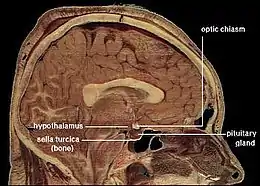

Sagittal post mortem section through the midline brain. The corpus callosum is the curved band of lighter tissue at the center of the brain above the hypothalamus. Its lighter texture is due to higher myelin content, resulting in faster neuronal impulse transmission.